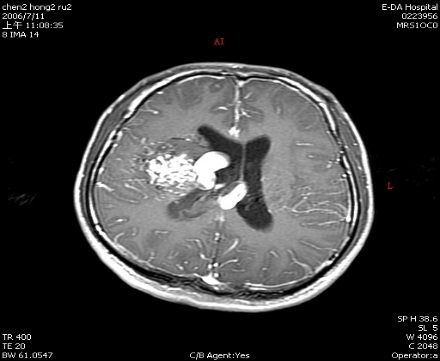

動靜脈畸形

手術前

手術後